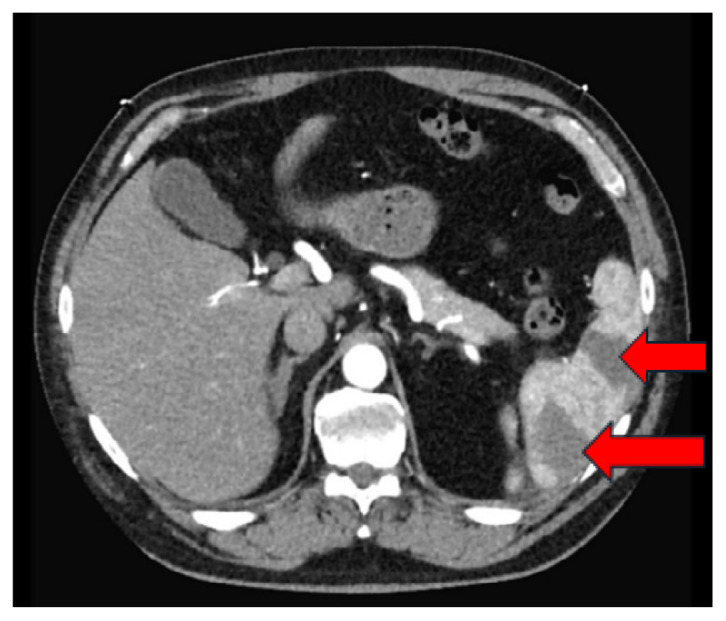

反向分析:左室血栓引起的脾梗死。

Working Backwards: Splenic Infarcts from Left Ventricular Thrombus.